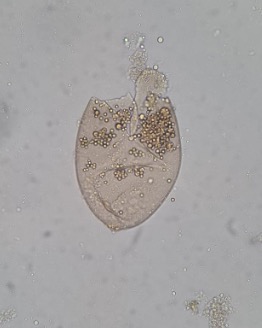

Imagem 1:

Gametócito com 1 núcleo mais avermelhado no centro.

Célula parasitada maior que a não parasitada.

Granulações de Schuffner.

Imagem 2:

Esquizonte maduro com um elevado número de Merozoítos

Não é possível a visualização das granulações de Schuffner no eritrócito parasitado pois este está quase a arrebentar.

Os Esquizontes jovens e maduros geralmente não aparecem no sangue periférico no Plasmodium falciparum. No entanto, se houver uma Parasitemia muito elevada (que não é o caso da imagem) estas formas desta espécie podem aparecer no sangue periférico.

→ Esquizonte maduro de Plasmodium vivax!